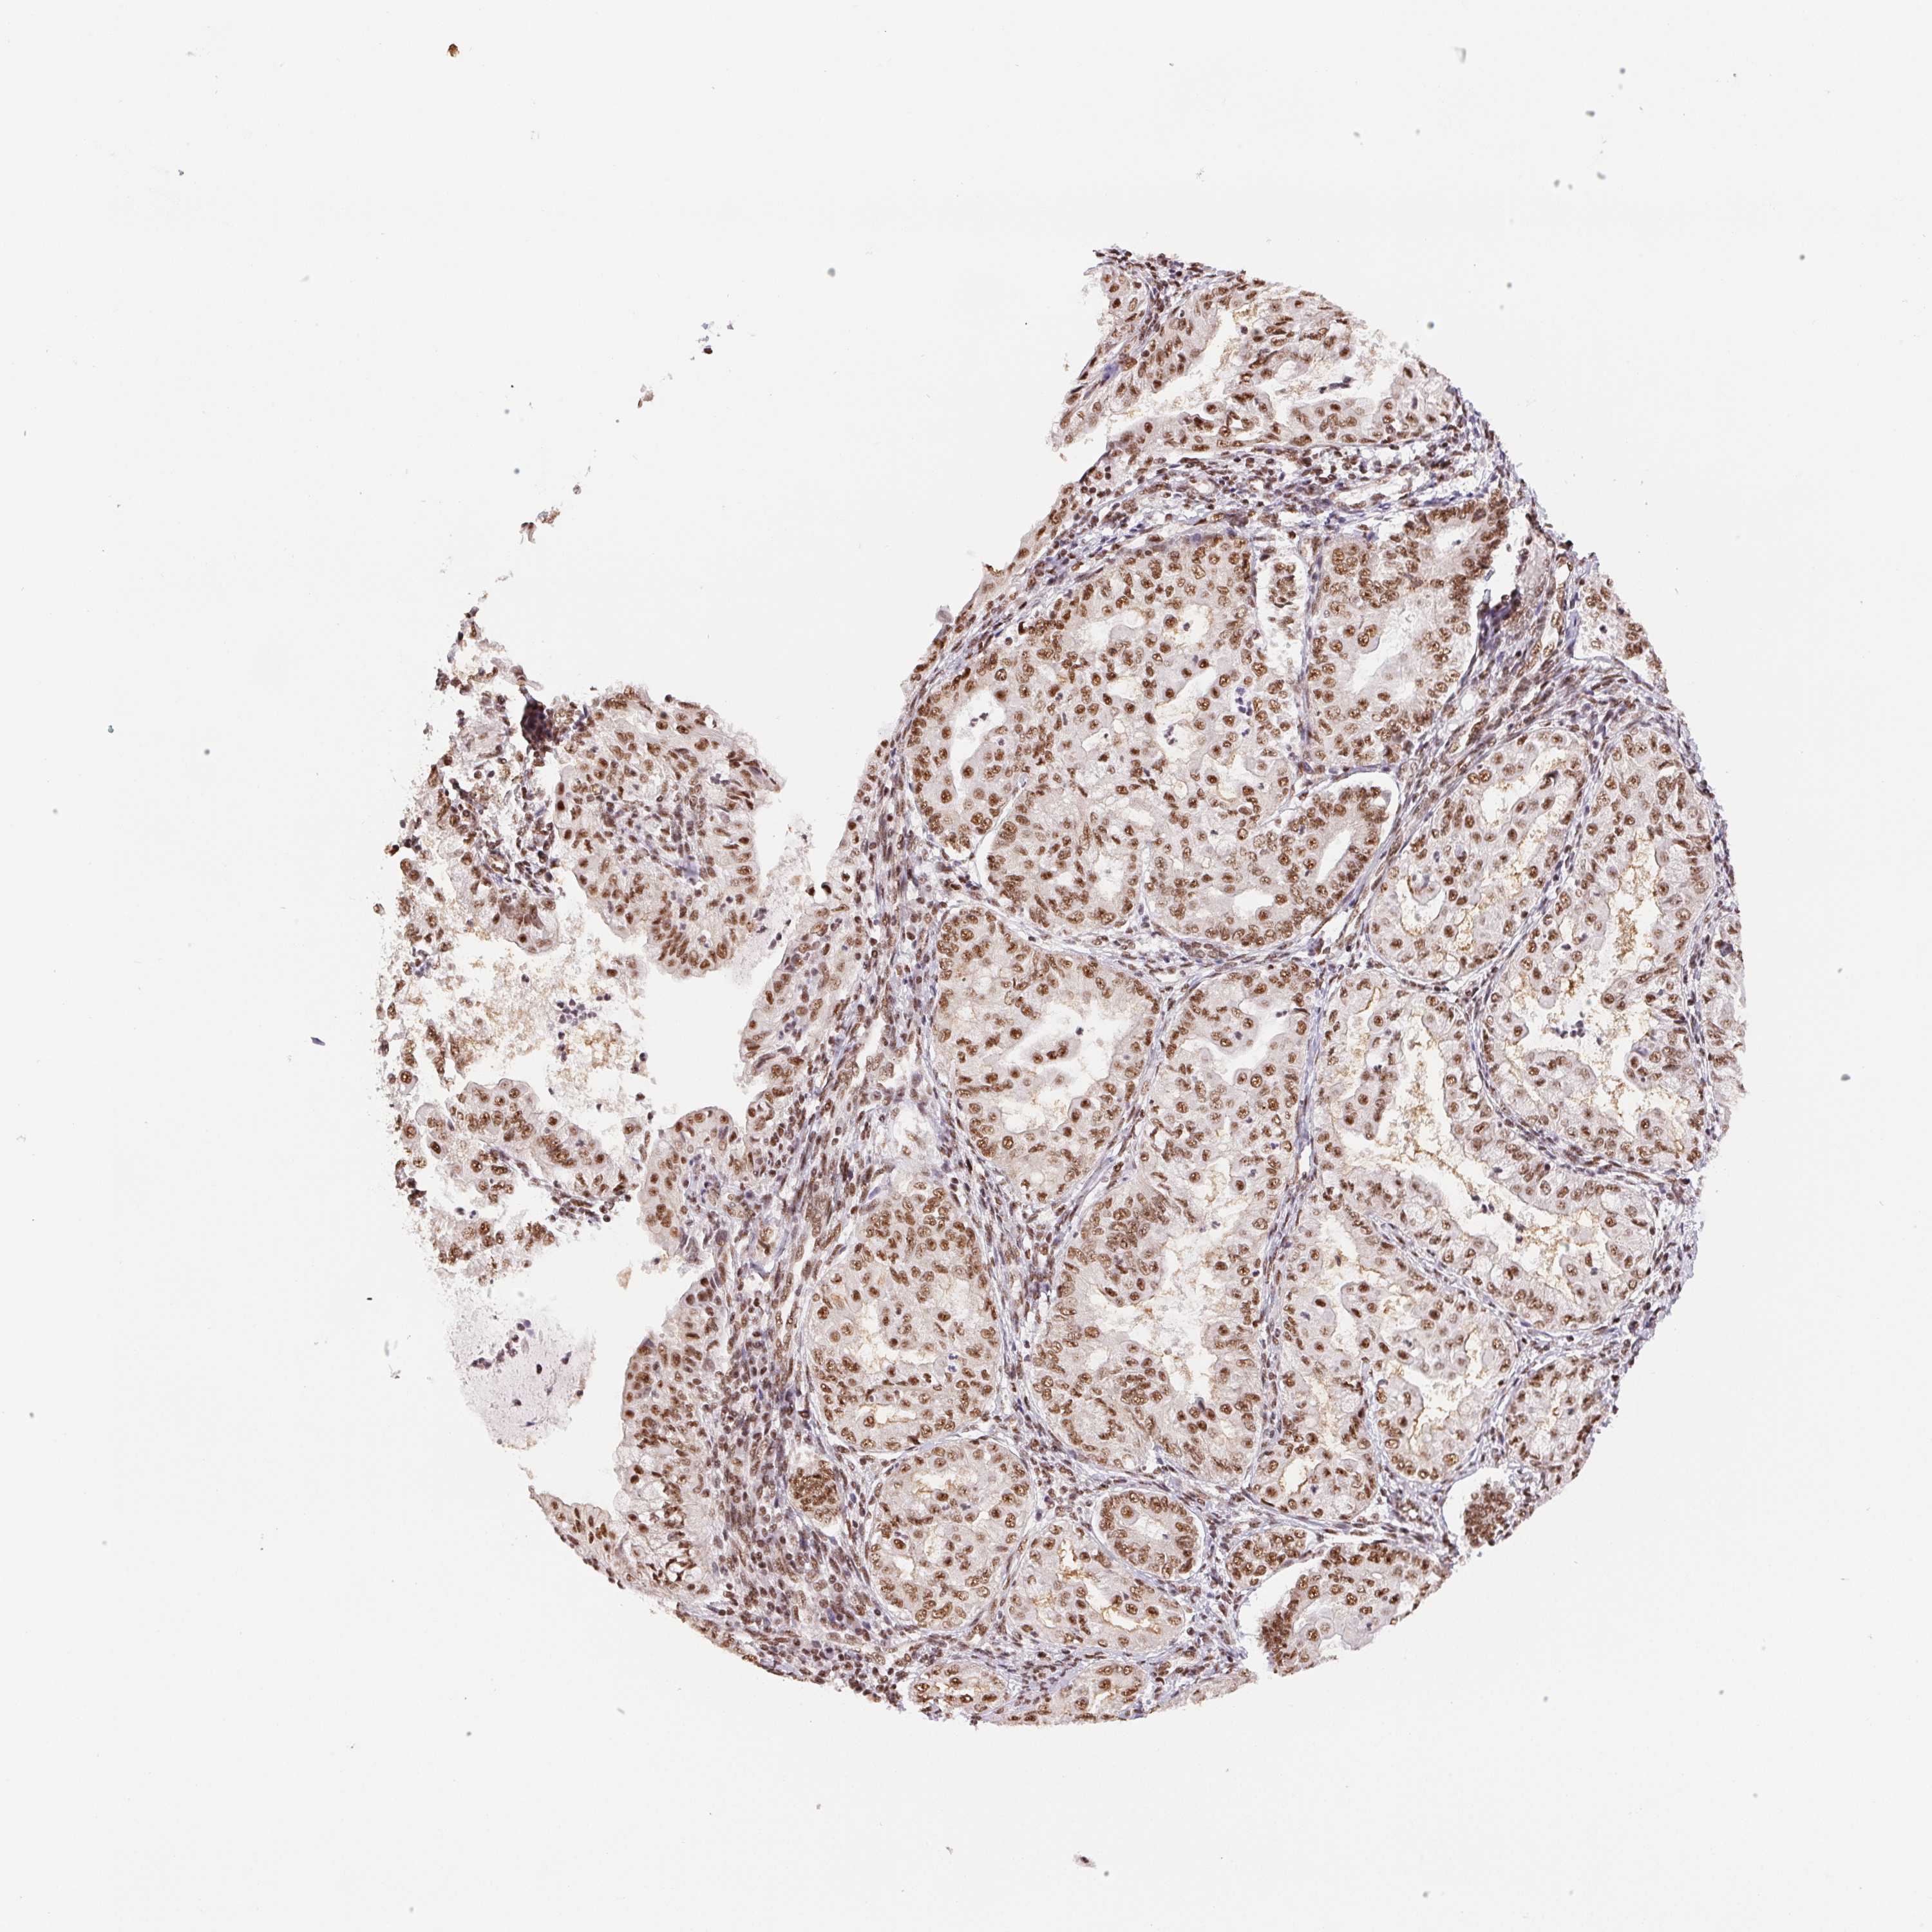

ENDOMETRIAL CANCER - Protein expressioni

A mouse-over function shows sample information and annotation data. Click on an image to view it in a full screen mode. Samples can be filtered based on level of antibody staining by selecting one or several of the following categories: high, medium, low and not detected. The assay and annotation is described here.

Note that samples used for immunohistochemistry by the Human Protein Atlas do not correspond to samples in the TCGA dataset.

Antibody stainingi

Antibody staining in the annotated cell types in the current human tissue is reported as not detected, low, medium, or high, based on conventional immunohistochemistry profiling in selected tissues. This score is based on the combination of the staining intensity and fraction of stained cells.

Each image is clickable and will lead to virtual microscopy that enables deeper exploration of all samples and also displays staining intensity scores, fraction scores and subcellular localization as well as patient and tissue information for each sample.

Antibody HPA048798

Staining

High

Medium

Low

Not detected

Intensity

Strong

Moderate

Weak

Negative

Quantity

>75%

75%-25%

<25%

None

Location

Nuclear

Cytoplasmic/membranous

Cytoplasmic/membranous,nuclear

Adenocarcinoma, NOS

Adenocarcinoma, metastatic, NOS